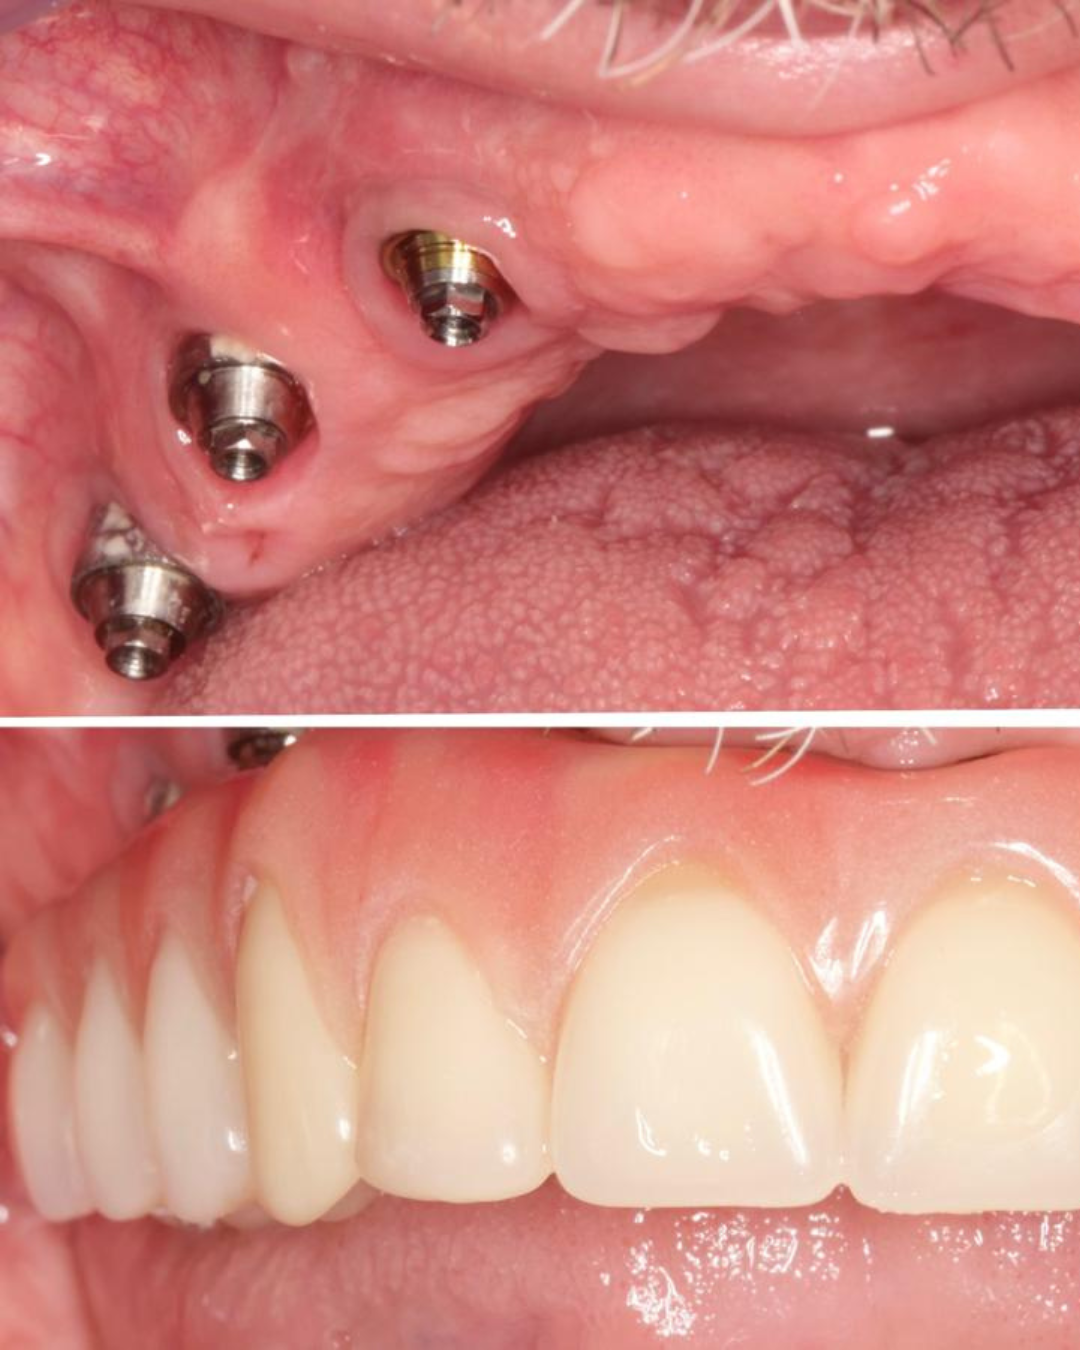

Soluções estéticas como implantes e próteses para um sorriso completo.